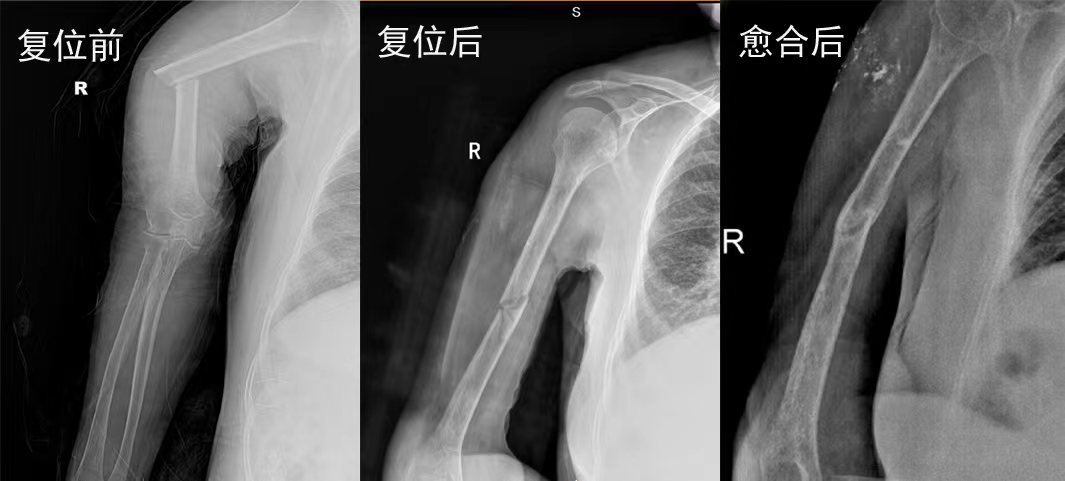

梁氏正骨-梁国利正骨案例